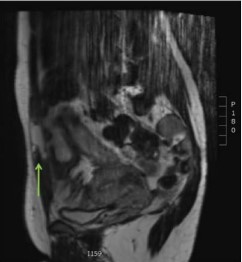

One week after discharge an MRI was performed to investigate the rupture in detail (Figures 4-6).

The MRI showed fluid in the right and left rectus abdominis muscle, with almost complete rupture of the muscle fibers. The fascia and linea alba were intact. Because of the intact fascia the conservative treatment with physiotherapy and pain medication

Figure 5: MRI T2, Sagittal view of the abdominal muscle.

was maintained. Follow up after 2, 6 and 11 weeks consisted of a visit to the outpatient clinic and an appointment with the doctor (author ET) who saw her during her initial visit to the ED and was uneventful. The patient started working out 10 weeks after the event without any problems.